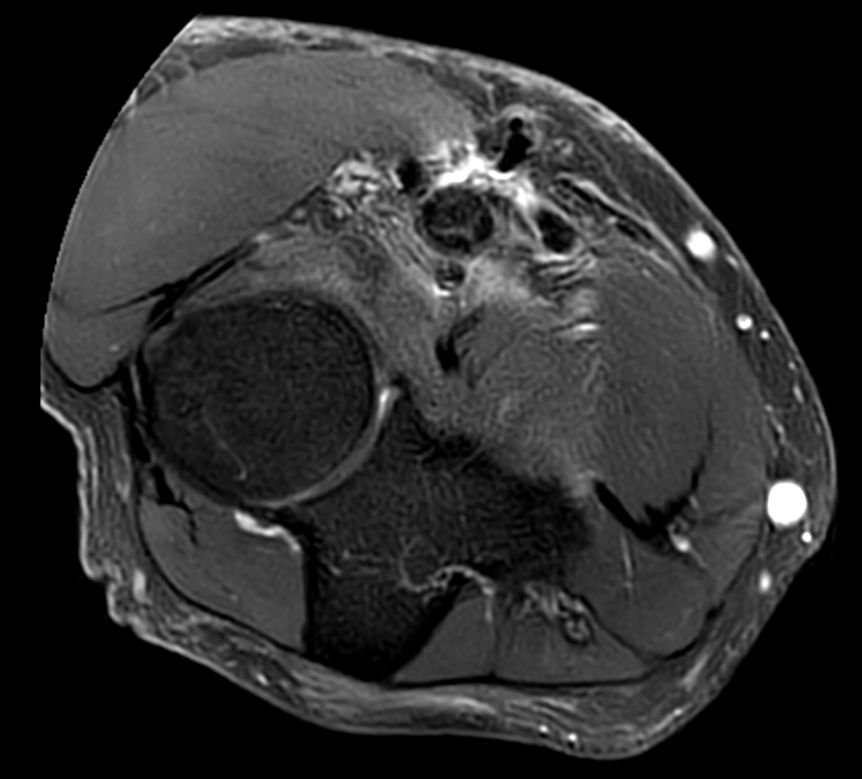

PDw TSE FatSat Compressed SENSE

T1w TSE Compressed SENSE

T2w TSE MultiVane XD FatSat